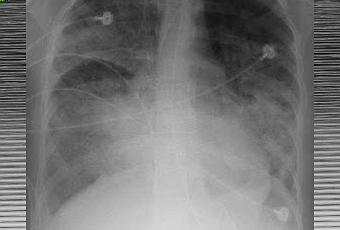

Syndrome de détresse respiratoire aiguë. Radiographie pulmonaire.

Source iconographique et légendaire: https://fr.wikipedia.org/wiki/Syndrome_de_détresse_respiratoire_aiguë